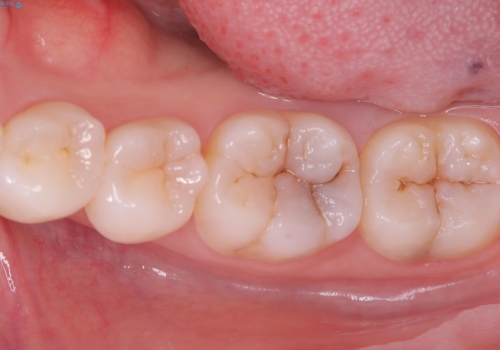

- 主訴:左下の奥歯がなんだか他の歯に比べて青白い気がする。虫歯じゃないか見てほしい。

左下6番目の歯の咬合面で虫歯が進行しており、プラスチックを用いた治療とセラミックを用いた治療を提案し、適合や材料安定性の良いセラミックインレーでのやり替えとなりました。